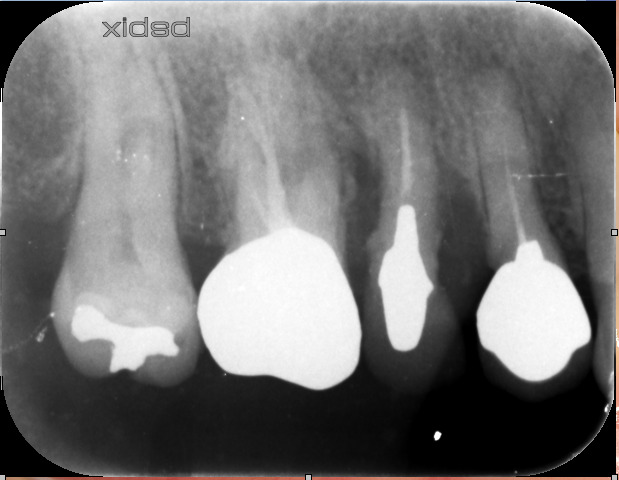

レントゲンを見ると、

右上の4.5.6番の骨が3分の2位無くなっている状態で重症の歯周病でした。

歯周ポケットも7mm程ありました。